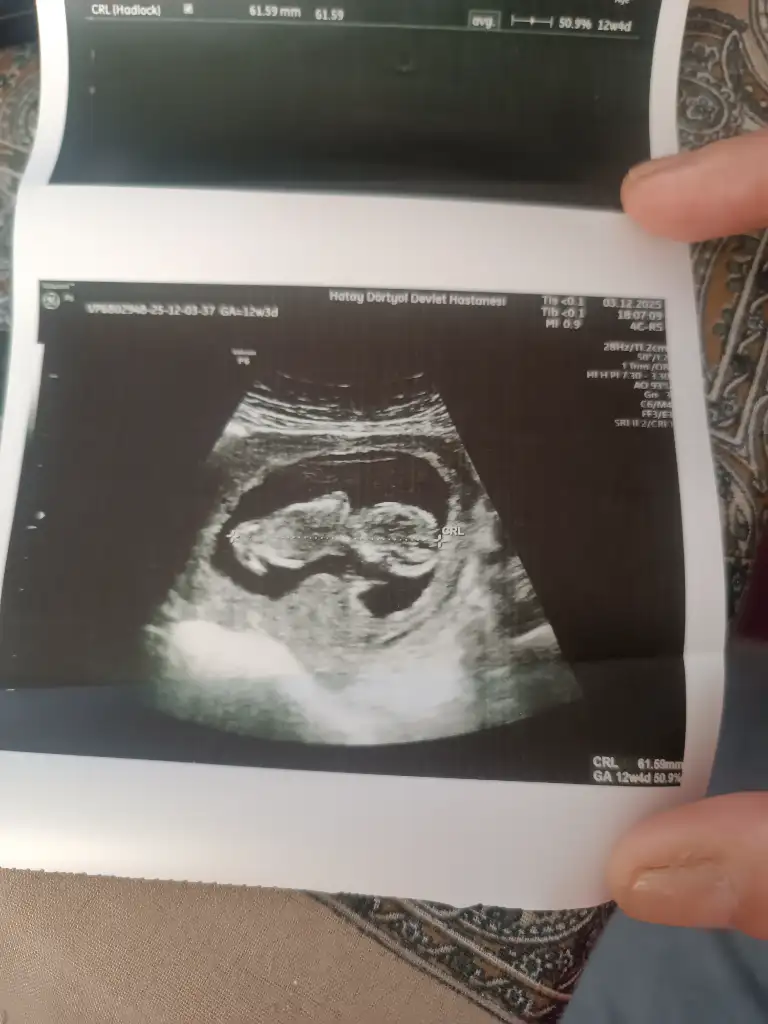

Her gittiğimde cinsiyet tahmini yapıyorum ama bukez kese değişmiş gibi yorum yaparmisiniz 🥰

• IMG_20251203_141602.webp

IMG_20251203_141602.webp

31,7 KB · Görüntüleme: 8